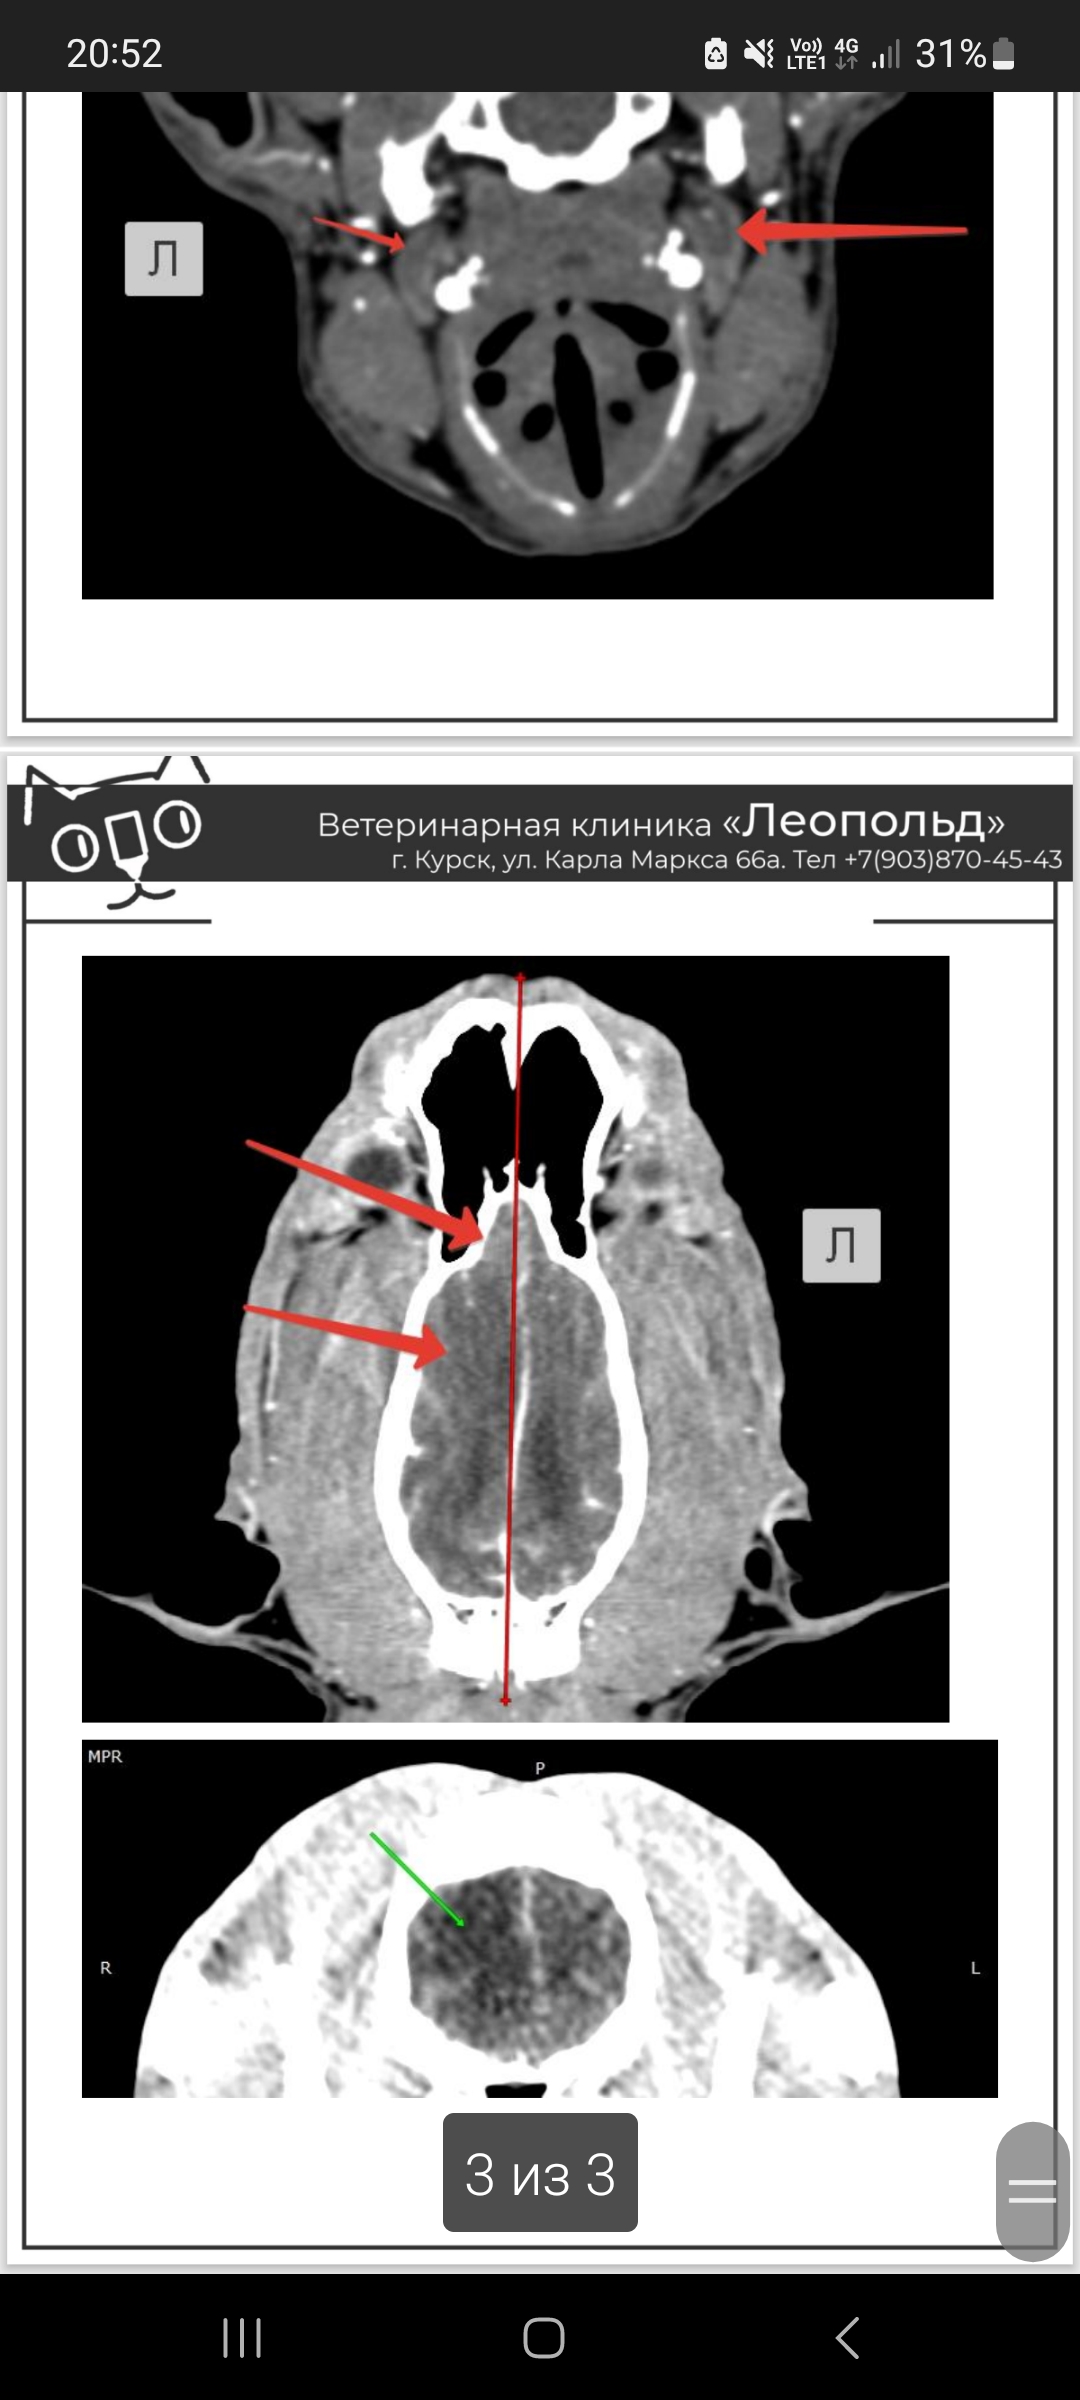

25 января у собаки случилось 4 эпилептических приступа через каждый час, срочно выехали в клинику, где нам оказали экстренную помощь. Далее мы делали обследование (анализы, кт, скрининг сердца) по которому невролог нам советует делать оперативное вмешательство. Принимаем паглюферал 3 два раза в день по одной таблетке. В ночь с 4 на 5 февраля собака стала скулить и беспокойно себя вести. В связи с чем не знаю (в период приступов выяснилась ложная щенность). Скажите можно ли как-то медикаментозно поддерживать собаку? Порода бультерьер, 9 лет. Анализы и результаты прилагаю.